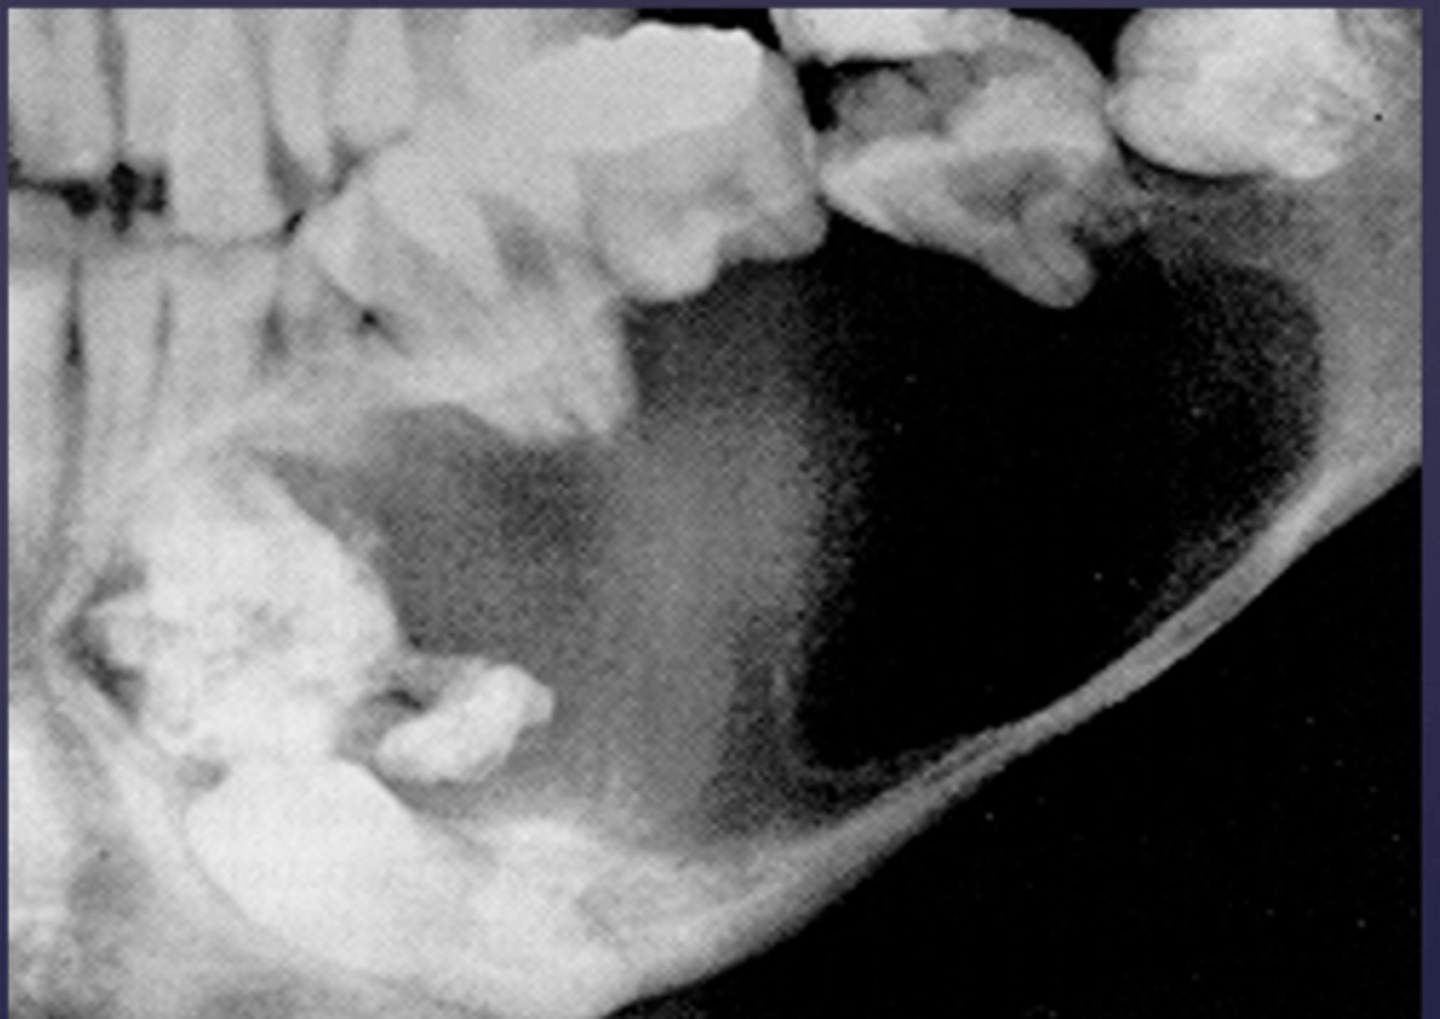

How would you describe the lesion?

- Well-defined corticated unilocular radiolucency in the left ramus causing expansion and thinning of

anterior and posterior walls of ramus, inferiorly below the inferior mandibular cortex and the coronoid process

- Dispalcement of the developing third molar.

What category would this lesion be part of?

Benign

What would be included in your D/D?

- OKC

- Unicystic ameloblastoma

- Dentigerous cyst